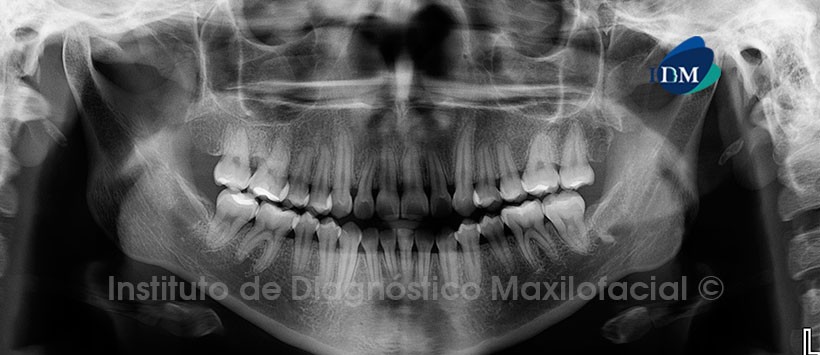

Paciente femenino, 23 años de edad es referido al Instituto de Diagnóstico Maxilofacial (IDM) para realizar su estudio previo al tratamiento de ortodoncia.

A la evaluación de la radiografía panorámica (Figura 1), observamos ausencia de las piezas 1.8, 2.6. y 4.8, así como también la presencia de un resto radicular a nivel del lecho alveolar de la pieza 3.8.